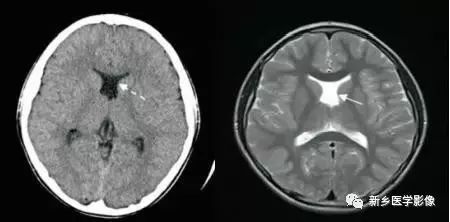

❹ 一侧室间孔阻塞

脑脊液主要产生于脑室的脉络膜丛。当一侧室间孔阻塞时,同侧侧脑室脉络膜丛产生的脑脊液不能进入三脑室,脑脊液在侧脑室内聚积,CT和MR检查表现为一侧侧脑室扩大,扩大明显时可有中线结构向对侧移位,主要原因有室间孔附近的肿瘤、囊肿、囊虫及炎性粘连。

确定一侧侧脑室扩大为室间孔阻塞所致的要点包括:

- 一侧侧脑室扩张明显,有张力;

- 透明隔向对侧移位;

- 扩一大的侧脑室周围没有能够导致该侧侧脑室扩大的其他可以解释的原因。

❺ 双侧室间孔阻塞

与一侧室间孔阻塞一样,双侧室间孔阻塞后,可表现为双侧侧脑室对称性或不对称性扩大,脑室扩大通常很显著,脑室周围多伴有间质性脑水肿,双侧室间孔阻塞的原因与一侧室间孔相同。可同时伴有导水管狭窄。

诊断要点:双侧侧脑室扩大很显著而三脑室大小正常。